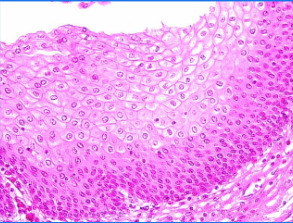

stratified squamous

Flat and irregular on free surface

Protect against abrasion